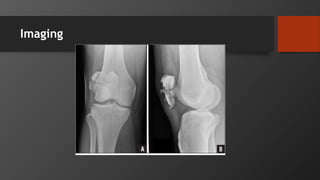

Tibial Plateau Fracture

• Imaging:

• X-Ray: AP, Lateral

• CT for preop planning, assessing articular depression

• MRI

• ABI if any differences in pulses between limbs